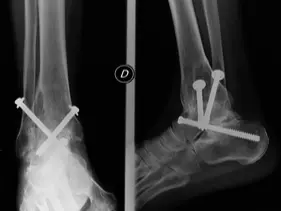

| Compartment Syndrome | Increased pressure within a closed fascial compartment, leading to reduced tissue perfusion, hypoxia, and irreversible muscle and nerve damage. Causes: Fractures (especially tibia/forearm), severe soft tissue trauma, arterial injury, burns, tight casts/dressings, post-ischemic reperfusion swelling, IV fluid extravasation, and bleeding disorders (e.g., hemophilia). High-Risk Notes: Pain may be absent in altered consciousness, children (monitor analgesia response), polytrauma, sedated/epidural cases, or concomitant nerve damage. Open fractures do not always decompress pressure. Gross/Clinical: -tense, shiny leg swelling with blisters in compartment syndrome.Imaging: - Intraoperative fasciotomy | History/Symptoms: Pain out of proportion to the injury (e.g., a “bursting” sensation), which is not relieved by analgesia. Clinical Features (The 5 P’s): - Pain with passive stretch (early, key sign; e.g., ankle dorsiflexion for leg, wrist for forearm). - Paresthesia (early). - Palpable tense swelling (shiny skin, blisters: clear=mild, serosanguinous=severe, bloody=worst; dusky/pallor skin). - Pallor, Paralysis, Pulselessness (late, ominous signs; pulses often palpable until late). Investigations: Primarily a clinical diagnosis (high suspicion key). Compartment pressure measurement can confirm: absolute pressure >30 mmHg or Delta Pressure (Diastolic BP - Compartment P) ≤ 25 mmHg. | Initial: ABCs, supplemental oxygen. Remove all circumferential dressings, casts (bivalve to skin), and splints. Elevate the limb to heart level (not above; higher reduces inflow). Correct any hypotension. Surgical: Urgent Fasciotomy if no response within 1h or confirmed pressure (prophylactic in high-risk like major osteotomy). Release all compartments/skin with long incisions; debride necrotic muscle via 4C’s (early: pink/red, soft, contracts/bleeds on pinch; late: dark, firm, no response); preserve neurovascular. Wound open (bulky dressing/splint, VAC, or boot-lace gradual closure); repeated inspections x48h; coverage in 3-5 days (skin graft usual; flap if nerves/vessels/bone exposed). | Cellulitis, Deep Vein Thrombosis (DVT), Arterial occlusion, Severe soft tissue injury without compartment syndrome; equivocal cases in polytrauma. | Complications: Volkmann’s ischemic contracture (permanent deformity, weakness, sensory loss, chronic pain). Contraindications (Fasciotomy): Confirmed >48h (irreversible damage, high infection risk from dead tissue); crush injuries with already necrotic muscle. |

| Open Fracture | A fracture with a breach in the overlying skin and soft tissues, creating communication with the external environment. All open fractures are considered contaminated (even small punctures; aka compound fracture). Causes: Can result from high-energy trauma (RTAs, falls, firearms; signs: degloving, crush syndrome, bone loss, segmental) or low-energy trauma. Contamination risk higher with farm/soil injuries, bites, delayed presentation (>12h), fecal/oral/soil/water exposure. Mechanism: Low/high velocity missiles (cavitation >300 m/s); in-out (cleaner) vs. out-in (dirtier). Gross/Clinical: ![]() | History: Mechanism of injury (energy, time, place, type/impact method), consciousness, wound size/bleeding amount, other injuries (often missed), tetanus status. Assessment: ATLS protocol (ABCDE) first (treat patient, not fracture; exclude shock/brain injury, monitor vitals; viscera exam: ribs=lungs/liver/spleen, pelvis=bladder/urethra). Examine wound (look/feel/move carefully post-splint), check distal neurovascular status, compartment syndrome. Photograph/remove gross contamination; cover with saline dressing. Classification (Gustilo-Anderson): - Type I: <1 cm wound, clean, minimal soft tissue. - Type II: >1 cm wound, moderate soft tissue (no stripping). - Type IIIA: Extensive soft tissue damage, but adequate bone coverage. - Type IIIB: Extensive soft tissue loss with periosteal stripping; bone exposed, requires flap coverage. - Type IIIC: Any open fracture with an arterial injury requiring repair. | Initial (ER): ATLS first. Cover wound with sterile saline-soaked dressing, splint limb, IV fluids (request blood if needed); traction if no distal pulse/deformity. Prophylaxis: Tetanus prophylaxis/serum and broad-spectrum IV antibiotics immediately (culture tissue/blood); clean major contamination. Surgical: Urgent debridement/irrigation within 6-12h (“Dilution is the solution to pollution”; pulse-irrigate 3-6-9L saline; excise non-viable tissue/foreign material, trim skin edges, remove dead muscle/detached bone, preserve N/V). Stabilization: external fixator (preferred severe; replace with cast post-infection); internal if clean/minimal. Wound closure delayed (primary if small/clean; secondary if contaminated/large). Early soft tissue cover. | The diagnosis is typically obvious. Key: Classify severity; identify associated injuries like compartment syndrome, vascular damage, or high-energy signs (e.g., crush). Differentials for contamination: Primary (field debris) vs. secondary (post-fixation if poor debridement). | Complications: Infection (cellulitis, osteomyelitis, chronic with sequestra/drainage, gas gangrene), tetanus; higher with delay/exposure/bites. - embolisms fat, thrombi others.. Case Insight: Unconscious patient (e.g., open tibia post-RTA): ABCDE/cervical collar, distal pulses/traction, admit for debridement; ankle fall: Splint post-ABC, assess neurovascular. |